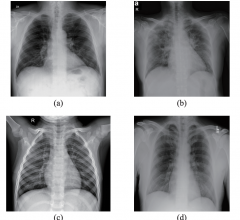

Lung Imaging

News and new technology innovations concerning how imaging technology for the lungs. This includes computed tomography (CT), X-ray and ultrasound imaging of the lungs to diagnose and monitor treatment for lung cancer, COPD, pulmonary embolism (PE), pneumonia, tuberculosis and COVID-19 can be found on this channel.